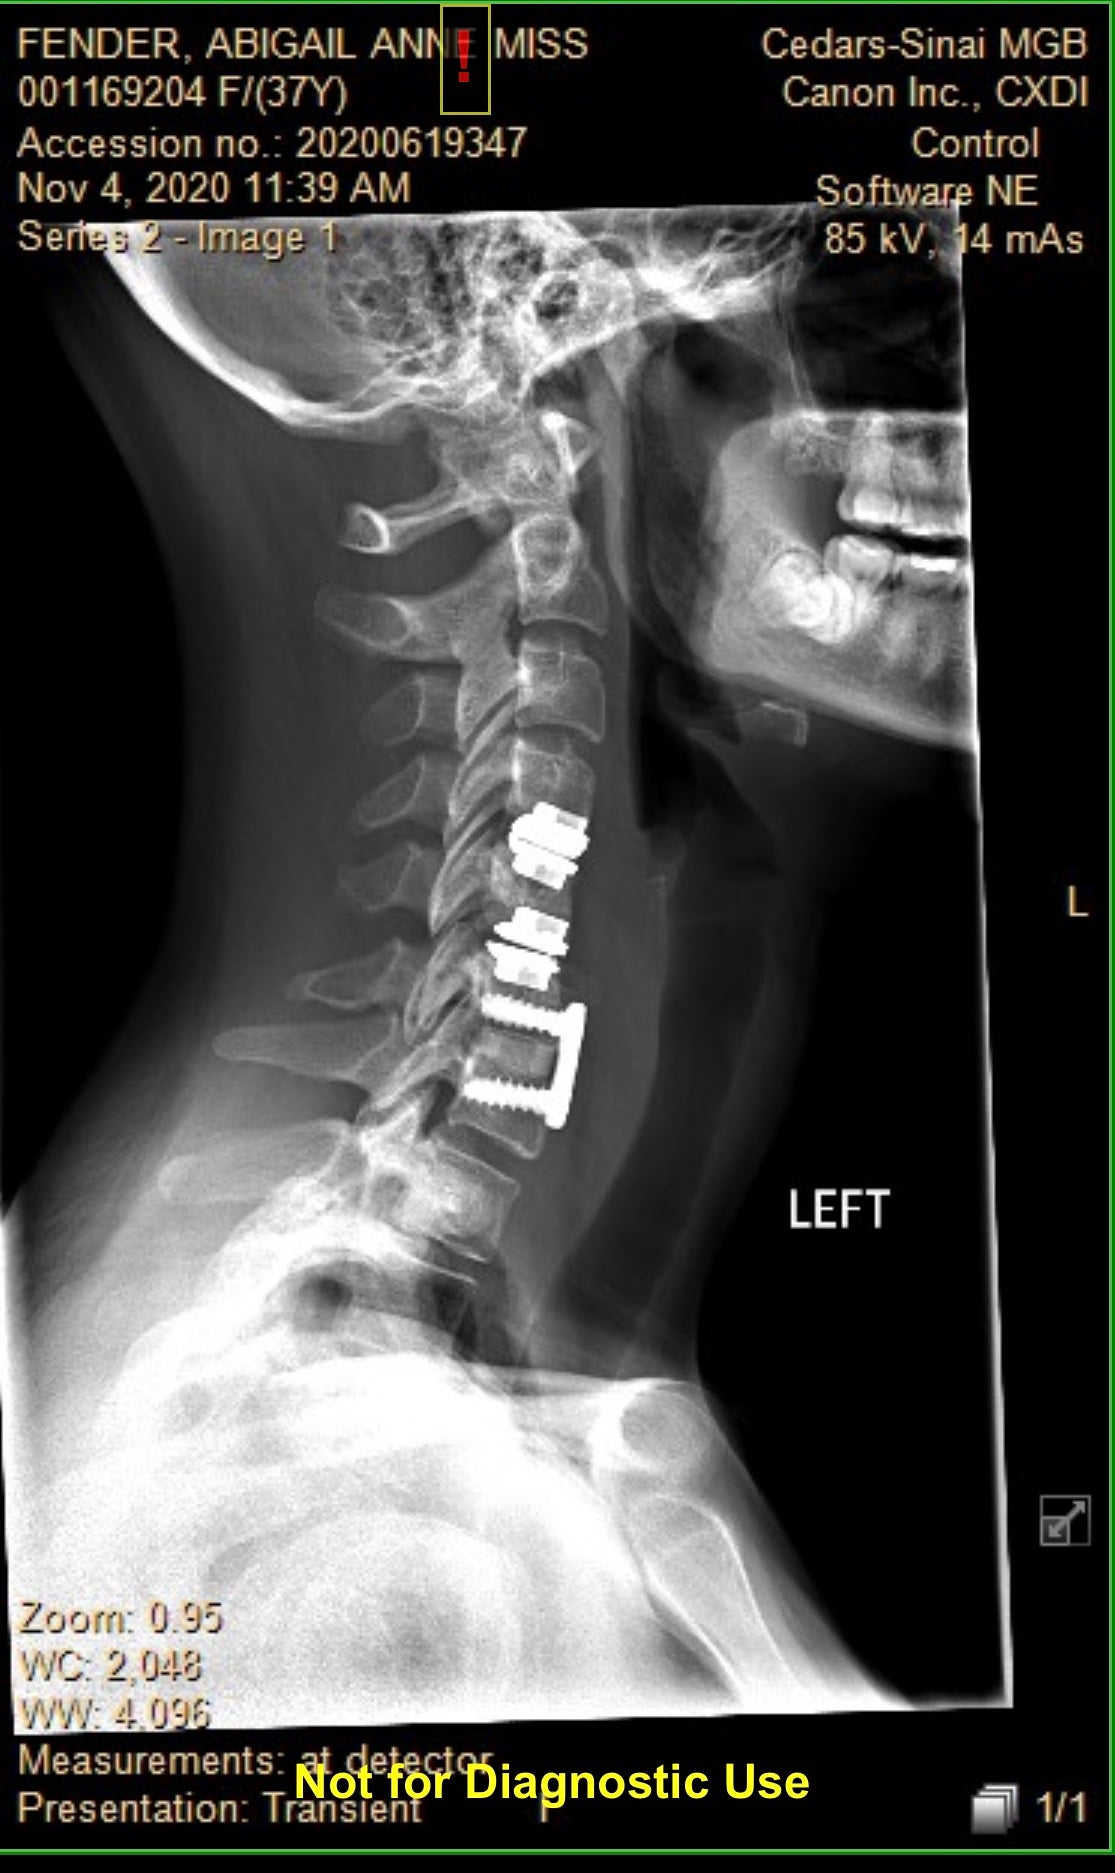

When Abby Fender woke up after surgery to fix a herniated disc, she was shocked to discover her vocals were “paralysed” and her Texas accent had disappeared.

The 39-year-old said: “It’s been incredibly difficult to be given any diagnosis, but many medical professionals don’t believe Foreign Accent Syndrome is real. I have been so disappointed, but I’ve gone through every test known to man, such as MRIs and CT scans, all to determine the cause of my speech dysfunction.

“I have been diagnosed with everything, from general speech dysfunction to Dystonia, a form of muscle spasm and contractions. However, nothing has ever pinpointed why I went to sleep with a southern accent and woke up sounding like this ... It’s so bizarre and scary not knowing what is causing this to happen.”

“I believe something happened during the surgery that may have had a serious impact on the Broca portion of my brain, which controls the way we say different words and our general pitch when speaking, but we’ll never know. It’s been frustrating on levels I cannot even describe, as knowing how and what I want to say, but being unable to verbalise it is a curse I wouldn’t wish on my worst enemy.“I am totally at the mercy of my brain and for the first time in my life, I don’t know how to control my voice, but I’m so grateful for the Foreign Accent Syndrome, as without it, I wouldn’t be able to speak at all.”